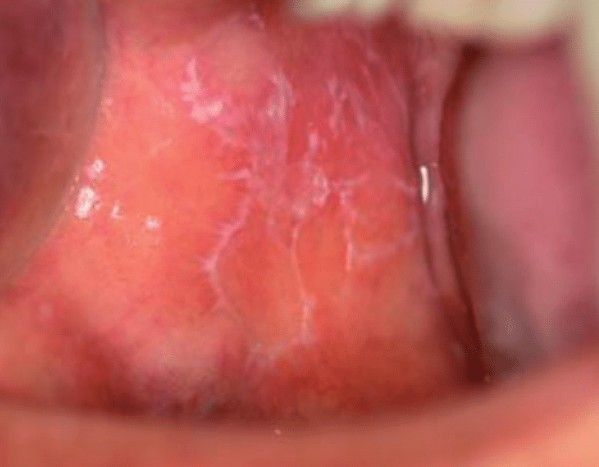

Десквамативный ("географический") глоссит следует отличать от кандидоза, красного плоского лишая, лейкоплакии, бляшек при вторичном сифилисе и аллергических стоматитов. При кандидозе налёт частично снимается со спинки языка. При этом обнажается покрасневшая гладкая поверхность, которая может кровоточить. Также кандидозные бляшки встречаются и в других отделах рта. При красном плоском лишае патологически изменённый очаг на языке образован мелкими папулами ("пузырьками" с содержимым) с "кружевным" рисунком — сеткой Уикхема.

![Сетка Уикхема при красном плоском лишае [33] Сетка Уикхема при красном плоском лишае [33]](/media/bolezny/glossit/setka-uikhema-pri-krasnom-ploskom-lishae-33_s.jpeg)

Сетка Уикхема при красном плоском лишае [33]